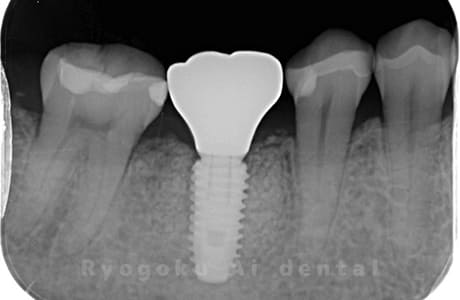

Case07

-

- 原因

- 右下6番歯根破折

- 治療内容

- インプラント治療

- 治療費用

- 約600,000円

右下の腫れが治らないとの事でご来院された患者様です。歯が割れていたため、抜歯を行い、骨に代わるお薬を入れ、インプラントを埋入致しました。経過良好で大変満足していただけました。

<リスク・副作用>

治療後、痛みや違和感、出血、腫れなどが出る事があります。喫煙者、糖尿病などの方の場合、歯が生着しない場合があります。